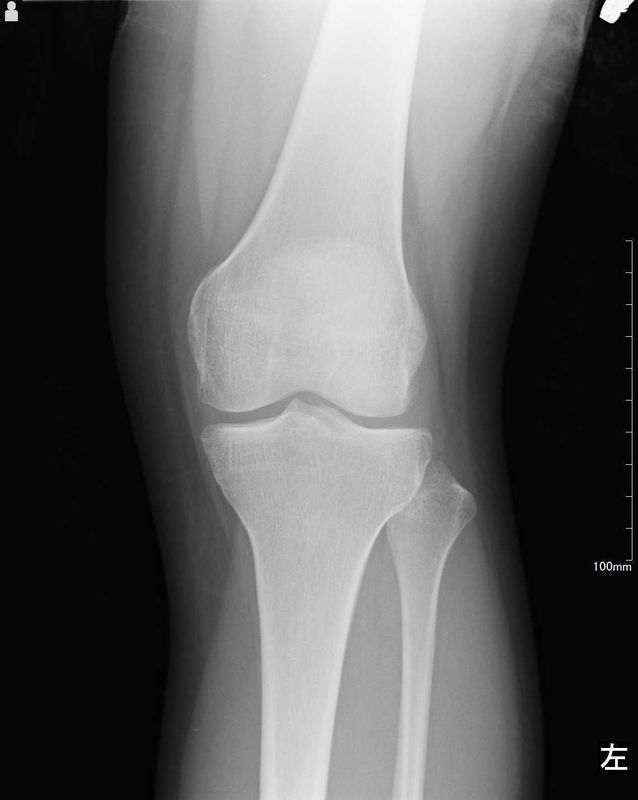

レントゲン所見

| 手術前 | 手術後 |

![]() ![]() | ![]() ![]() |

| 明らかな変形などの病変なし | 術後の変形などはなく術前と変化なし |